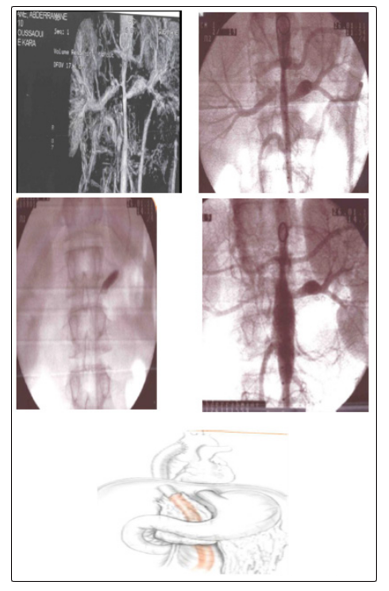

In our series, we have performed 04 TLA-stent of supra-aortic trunks, 03 TLA-STENT of subclavian, Endoprosthesis for aneurysm of the thoracic aorta and the abdominal aorta (Fig1.) 05 TLA -renal arteries (Fig.2), 02 ATL-Stent of iliac arteries, 01 Endoprosthesis for coarctation of the aorta (Fig.3) and TLA of the abdominal aorta and right renal artery for aortic hypoplasia, surgically taken after failure of the angioplasty (fig.4).

Figure 4: young male, 16 years old,

Hypertension uncontrolled under triple therapy.

Lesion: length tubular stenosis of the abdominal aorta and tight stenosis of the right renal artery.

Procedure: Medical Treatment. 1st time: abdominal endoprosthesis +angioplasty of the right renal artery

Evolution: failure of the endovascular treatment.

2nd time: conversion with aorto bi-iliac bypass from the ascending aorta

Evolution: good with stabilization of the blood pressure. The surgical treatment of our patients was in all cases motivated by the severity of hypertension that was resistant to medical treatment and the failure of angioplasty, either by difficulty of catheterization, dissection or restenosis.